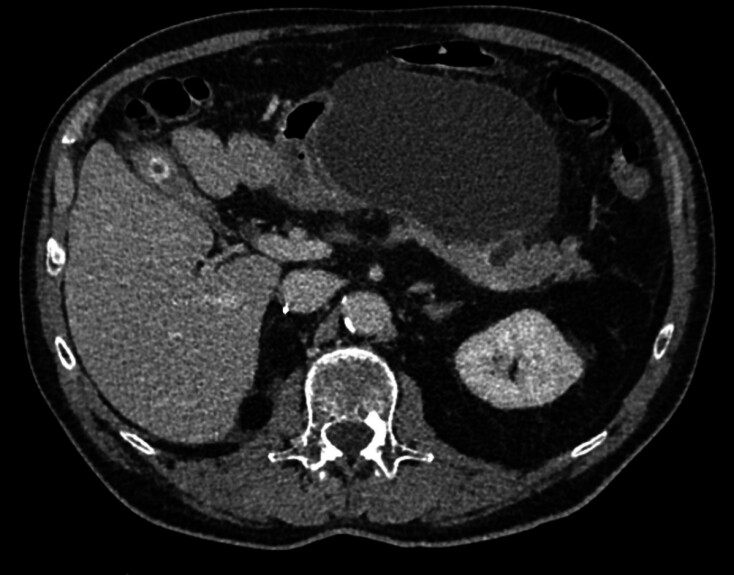

Patients and methods: This retrospective, observational study included consecutive patients referred for EUS-RFA of pancreatic RCC metastases. EUS-RFA was performed through 18G or 19G dedicated RFA needles. Effectiveness of EUS-RFA treatment was defined by necrosis with no contrast enhancement or lesion disappearance, determined by contrast-enhanced computed tomography (CT) scan, at 2 to 5 months post procedure, 1 year, and at the end of follow-up. Safety was assessed per and post procedure.

Results: Between January 2015 and January 2021, eight patients with 11 lesions were treated and median time from RCC diagnosis to pancreatic metastases RFA was 8.5 years (1-15). Mean lesion size was 13.9 mm (± 3.9). Technical success assessed by immediate post procedure contrast-enhanced CT or Doppler was 100%. At the first CT scan follow-up, complete response was 45.4% and partial response was 27.3%. At 1 year, complete response was 45.4% and partial response was 27.3%. Three patients had multiple EUS-RFAs. Adverse events occurred in 3 patients (mild acute pancreatitis, abdominal pain, and pancreatic fistula with retro-gastric pseudocyst).